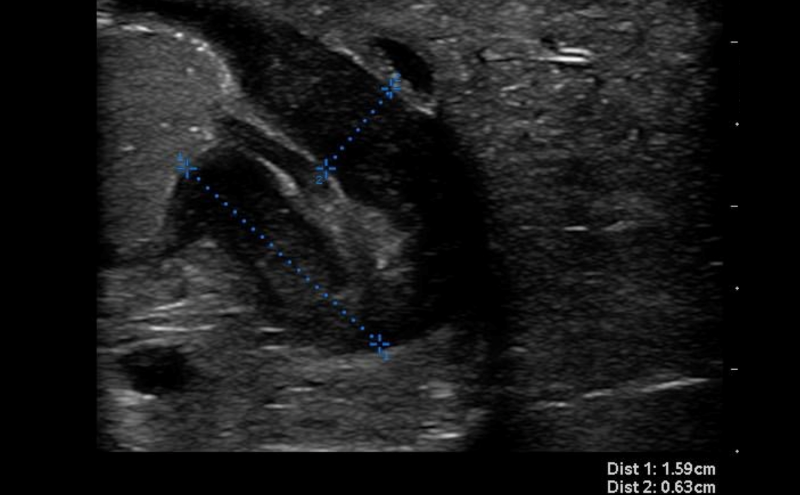

- Thickness of the pyloric muscle can be measured in the long or short axis view

- Figure 7. Hypertrophied pyloric muscle in short axis measuring 5.5mm

- A thickness of ³3mm is considered abnormal or hypertrophied